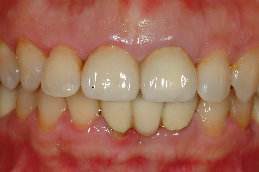

患者蔡小姐10年前,因為蛀牙,因而製作右上正門牙及左上正門牙共2 顆,但由於長期金屬黑邊露出、陶瓷龜裂,相當不美觀,並且右上正門牙的牙齦腫脹病患經介紹至本診所,尋求顯微根管治療及審美牙科治療,希望能徹底解決此問題。

一、正面觀時(圖一),金屬邊緣明顯可見,陶瓷龜裂,陶瓷厚度明顯不足。